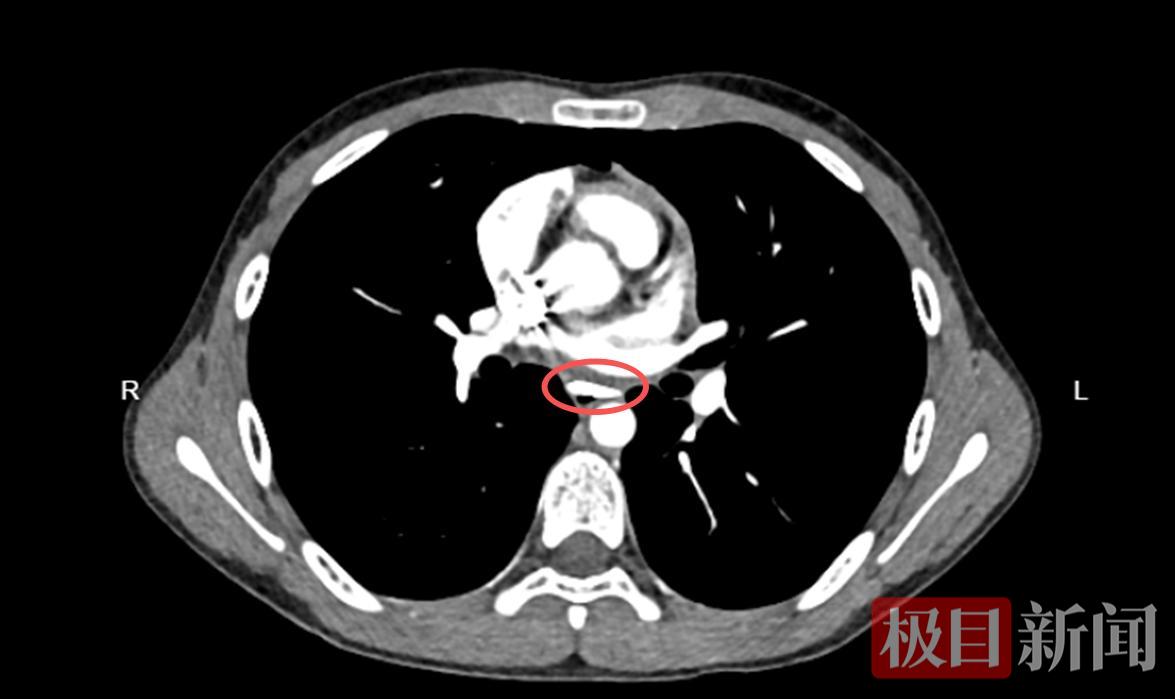

抵院后,医护人员为小轩完善了胸部增强CT检查,结果显示:异物位于胸段食管腔内,大小约26毫米×16毫米×5毫米,形状为三角形,像一块小“匕首片”卡在食管中,距离主动脉仅约1.1毫米,随时可能刺破血管,引发生命危险。

CT检查下的食管异物